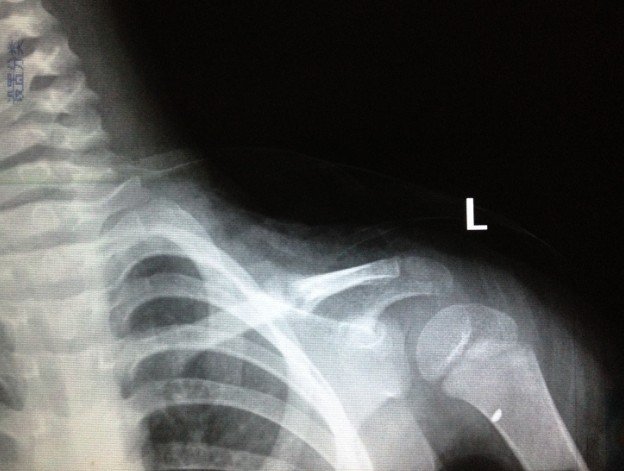

宝宝3岁半出车祸左锁骨骨折

患者信息:女 3岁 贵州 遵义 病情描述(发病时间、主要症状等):2012.10.7日发送车祸,X片确诊为左锁骨骨折。当天就打上八字绷带。想得到怎样的帮助:现在已经自行把八字绷带取下,请问这样做可以吗?因为孩子的腋下已经开始有轻微溃烂的症状(掉干壳壳)前段时间因为出车祸导致孩子的左锁骨骨折,去医院打了八字绷带,刚好一个月去医院复查,医生说已经开始长曾经治疗情况及是否有过敏、遗传病史:无

8字绷带笼殊还是没急着取下来,,才一个月,虽然骨痂生长饥训明显,,骨折断端对位对线也不错, 但仍不能绣殊崭太掉以轻心。再绑一个月估计才可去。 腋下涂点抗生素软膏就行。